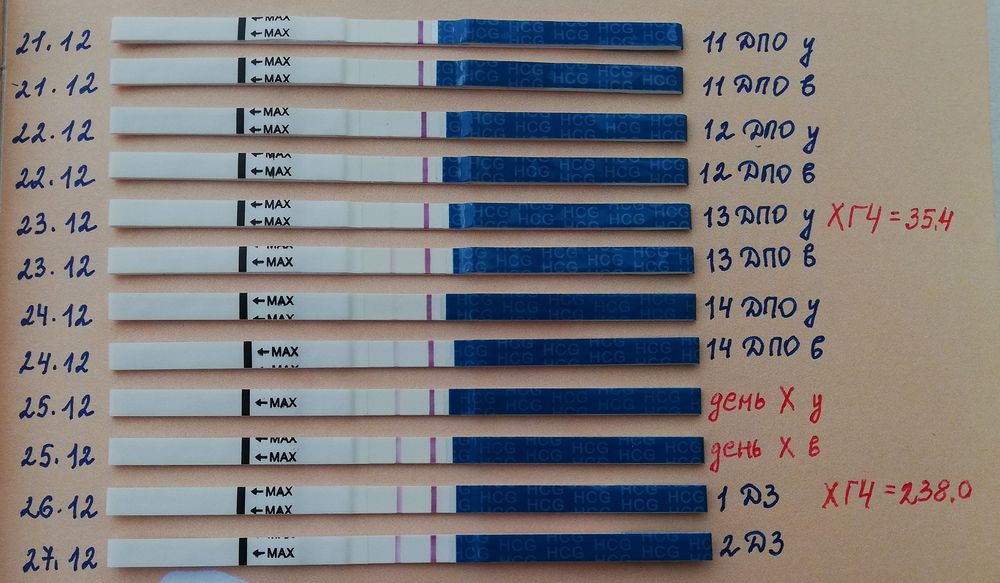

У меня полоски были не очень яркие (мамачек) и даже на второй день задержки не сравнялись. Но все равно по итогу все хорошо! 🩵

Яна, пожалуйста 😁 я дотошная 😂 сохраняла на память) ну и отслеживала четко, тк лежала на сохранении с кровотечением 3 недели.

Это примерно 11-12 дпо, хгч 103.

Тестовая ярче контрольной стала через 2 дня.

Это примерно 11-12 дпо, хгч 103.

Тестовая ярче контрольной стала через 2 дня.